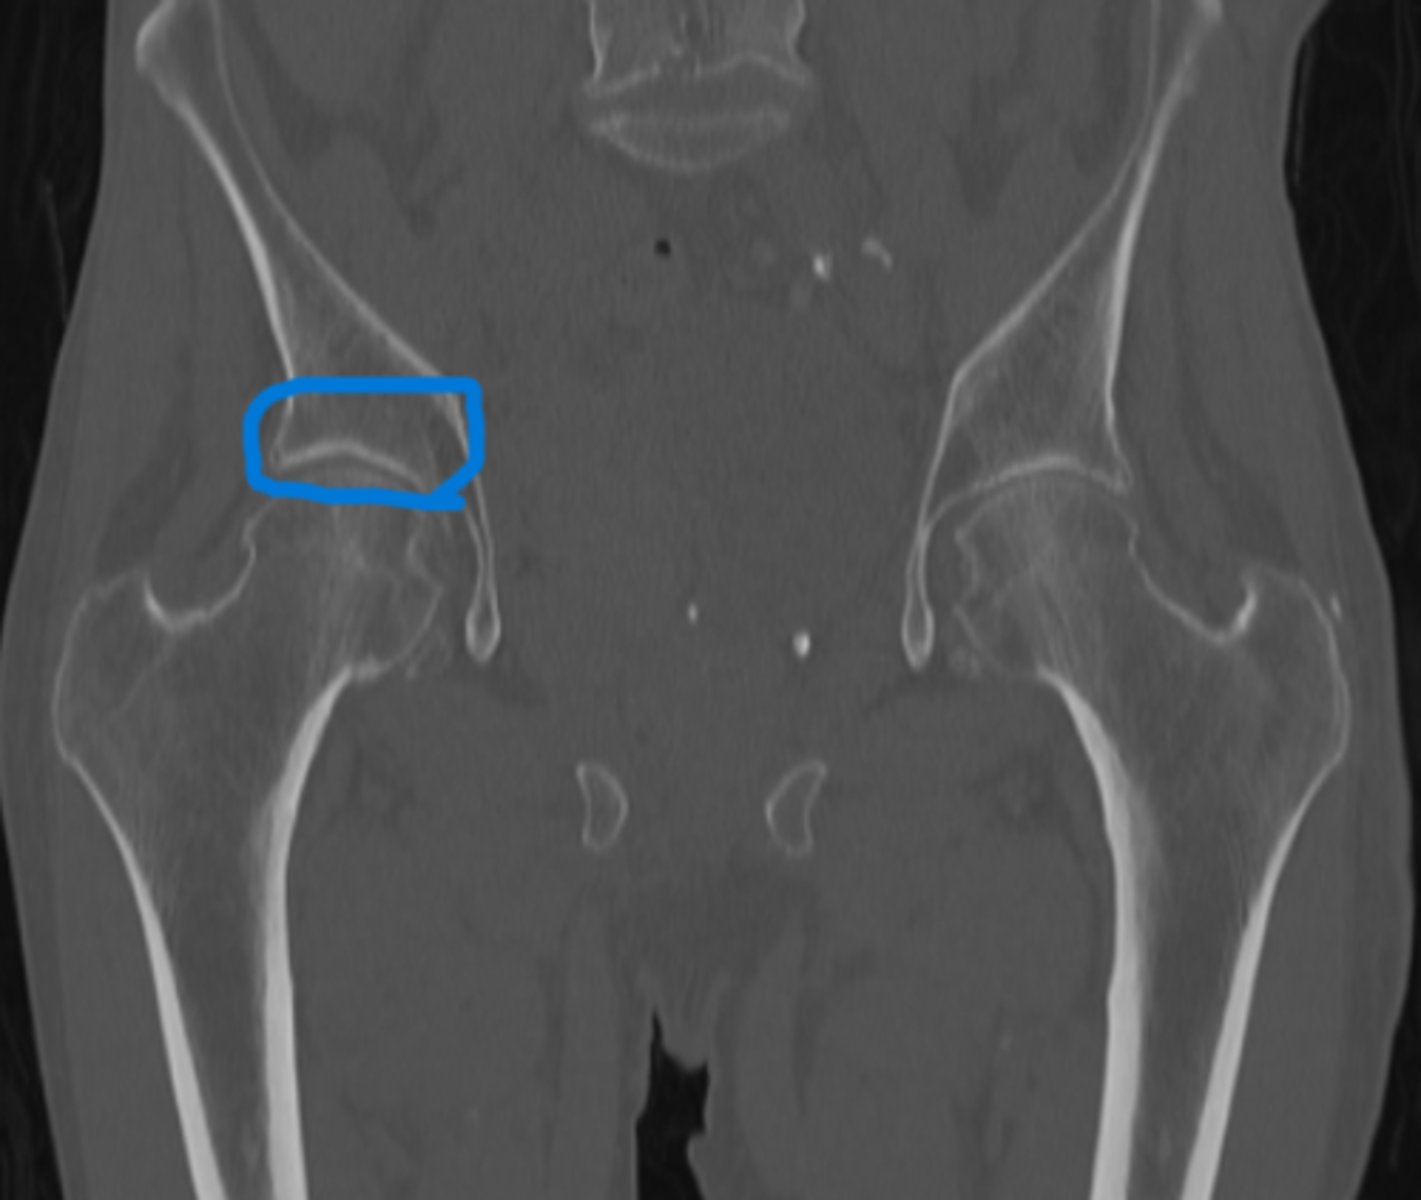

Colitis

What pathology is circled in blue